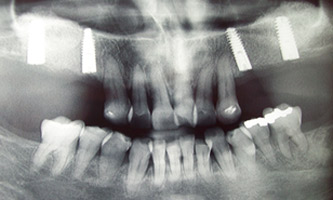

poslije

Kirurgija / implantologija